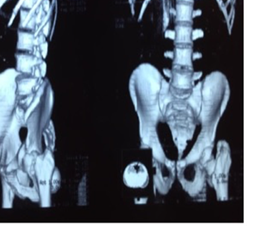

Material y Métodos: Reporte del caso

Presentamos el caso de un paciente de 49 años, trabajador de la construcción, sin patología previas, procedente del interior del Uruguay, quien otorgó su consentimiento verbal y escrito para la publicación de su caso. Sufre un accidente automovilístico en febrero del 2019, viajando como acompañante en asiento trasero sin cinturón de seguridad, sufriendo lesión de cadera izquierda al impactar la rodilla con el respaldo del asiento delantero. De la valoración inicial al momento de la asistencia en el lugar, no presenta lesión de cráneo, raquis, tórax ni abdomen y se constata miembro inferior derecho acortado, tumefacción en raíz de muslo y parestesias de miembro inferior derecho en territorio del nervio ciático poplíteo externo. Los pulsos distales estaban presentes y no presentaba otras lesiones del sistema músculo esquelético ni compromiso vascular. No se realizó ninguna maniobra sobre la cadera del paciente, ni en el lugar del accidente, ni en el centro asistencial. En la radiografía de frente, absolutamente atípica, se diagnostica luxación de cadera izquierda con fractura de cuello femoral, y el fragmento epifisario en dirección inversa (cuello hacia el acetábulo, y cabeza hacia el macizo trocantérico) (figura 1). La tomografía confirma luxación posterior del fragmento con la disposición antes mencionada, sin lesión ósea de la cabeza femoral, ni del acetábulo (figura 2, 3, 4, 5).

Figura 5: Tomografía reconstrucción 3D